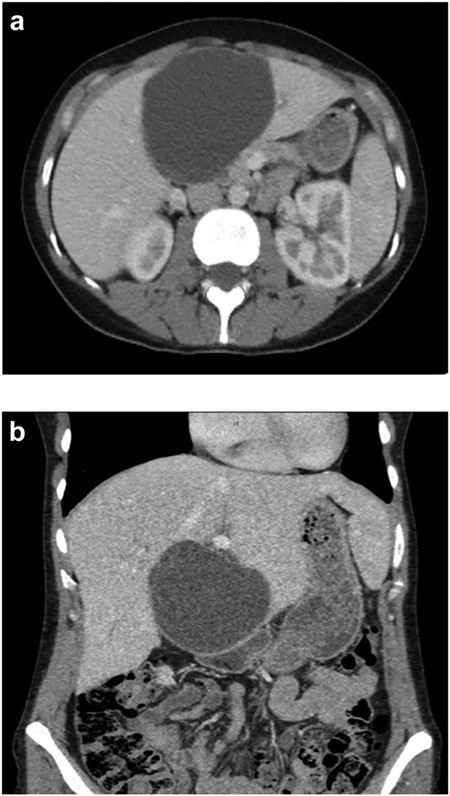

Pre-operative ERCP demonstrating compression of the common hepatic duct.

A 35-year-old female with a medical history significant for acute biliary pancreatitis status post laparoscopic cholecystectomy, presented to the surgery clinic as a new consult for a large cystic liver mass with increasing abdominal pain for 2 weeks. Patient reported suffering from severe pain in right chest, shoulder and diffuse abdominally that worsened with standing. Patient complained of inability to inspire due to pain and a 10-pound weight gain over 2 months. She confirmed decreased appetite especially with solids, nausea and emesis, alternating constipation and diarrhea, bruising, and pruritus at night. Computed tomography (CT) scan demonstrated a peripherally septated 10 x 7 cm cystic mass in the liver with intrahepatic biliary dilation (Fig. 1). The patient was referred for endoscopic retrograde cholangiopancreatography (ERCP) to establish preoperative biliary anatomy and was found to have moderate compression of the common hepatic duct managed with a right hepatic biliary endoprosthesis (Fig. 2); no obvious communication of the biliary tree with the cystic lesion was seen. Patient symptoms persisted despite optimizing with a protein-rich liquid diet; thus, the decision was made to proceed with the surgical plan for an open partial central hepatectomy. The patient was taken to the operative theater. After induction of general anesthetic, an upper midline incision was made. Inspection of the abdomen and liver showed no metastatic lesions grossly or with ultrasonographic imaging. The cyst was visible upon entry into the abdomen with no solid component to the mass in proximity to the cystic neoplasm. The second portion of the duodenum was adherent to the cyst with inflammatory adhesions and was quite boggy. A partial central hepatectomy was performed; a 3 mm biliary duct was found communicating to the cyst only with no drainage to the minimal liver parenchyma that was removed (Fig. 3). The cyst was resected en-bloc and was sent for permanent section (Fig. 4), which diagnosed the tumor as a low-grade mucinous cystic neoplasm measuring 8.5 × 7.2 × 6.4 cm. Microscopy revealed a smooth-walled, multiloculated cyst filled with a yellow-golden, semi-transparent and mucinous fluid (Fig. 5a–c). The cyst was lined by a mucinous epithelium with ovarian-type stroma. No high-grade dysplasia or malignancy was identified. The postoperative course was uneventful, and the patient was discharged on postoperative day 6. At the 4-week postoperative visit, the patient was healing well with some incisional soreness; patient was seen for removal of her biliary endoprosthesis, and ERCP found left sided intrahepatic duct biliary dilatation including a small biliary fistula from the left system (Fig. 6) with the appearance of torque on the extrahepatic biliary tree. A biliary endoprosthesis was left in place, and the patient returned for repeat ERCP 4 weeks later with resolution of all findings (Fig. 7). At present, patient remains alive with no signs of recurrence.